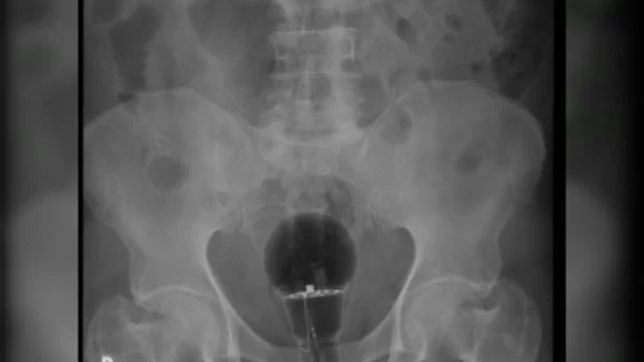

No entanto, exames de imagem mostraram que uma lâmpada foi enfiada em seu reto.

“O objeto não era palpável ao toque”, afirmou o gastroenterologista Julian Pylori, que fez o atendimento, em um tweet. O médico usa as redes sociais com frequência para compartilhar atendimentos inusitados.

Objetos como este, que correm o risco de se quebrar, tem de ser retirados do corpo em procedimentos cirúrgicos. No entanto, segundo reportagem da TV Azteca, foi possível succionar a lâmpada porque ela era feita de plástico.